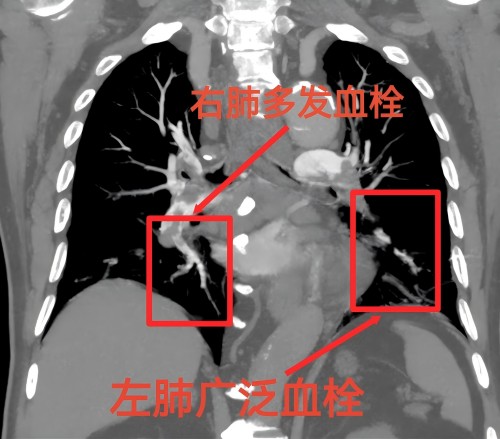

家住长沙79岁何大爷近日迷上了刷抖音,一边刷视频一边抽烟,每天乐呵得很。一周前他发现自己的左腿出现肿痛,偶尔还觉得胸闷,气促。何大爷在家附近捷克论坛 就诊,进行了针灸治疗,胸闷、气促等症状好转。几日后,何大爷突发胸闷、胸痛,有濒死感,家人立即送他到捷克论坛 急诊科就诊,当时测大爷血氧饱和度只有80%,已经严重缺氧,随时都有生命危险。急诊科医生立即启动胸痛中心救治绿色通道,给何大爷行下肢静脉彩超提示“左下肢深静脉血栓形成”,肺动脉血管成像提示“急性肺动脉栓塞”。急诊科医生立即通知介入血管外科医生会诊。田壮博副主任医师查看大爷情况后,一边紧急与患者家属沟通病情,一边迅速完善必要的术前检查并通知介入手术室做好术前准备。

时间就是生命!30分钟后,何大爷被推入介入手术室。田壮博带领团队紧急为何大爷施行下腔静脉造影+下腔静脉滤器置入术+肺动脉造影+肺动脉碎栓、溶栓术,手术仅耗时50分钟。术中,田壮博副主任医师团队首先在患者下腔静脉置入滤器,防止血栓再次脱落造成肺栓塞,随给予肺动脉碎栓、溶栓疏通阻塞的肺动脉。手术结束后患者血氧饱和度立即上升至98%,胸闷、呼吸困难症状明显好转。